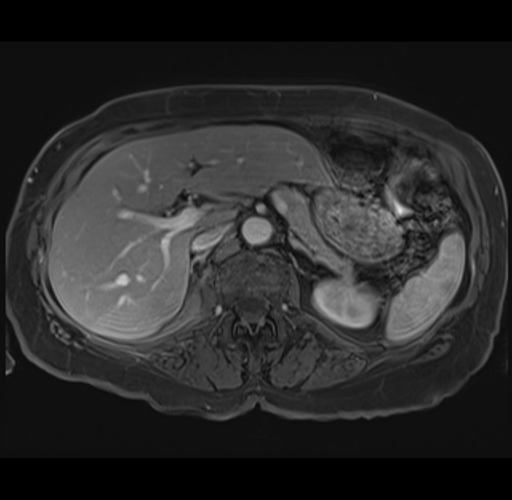

MRI T1